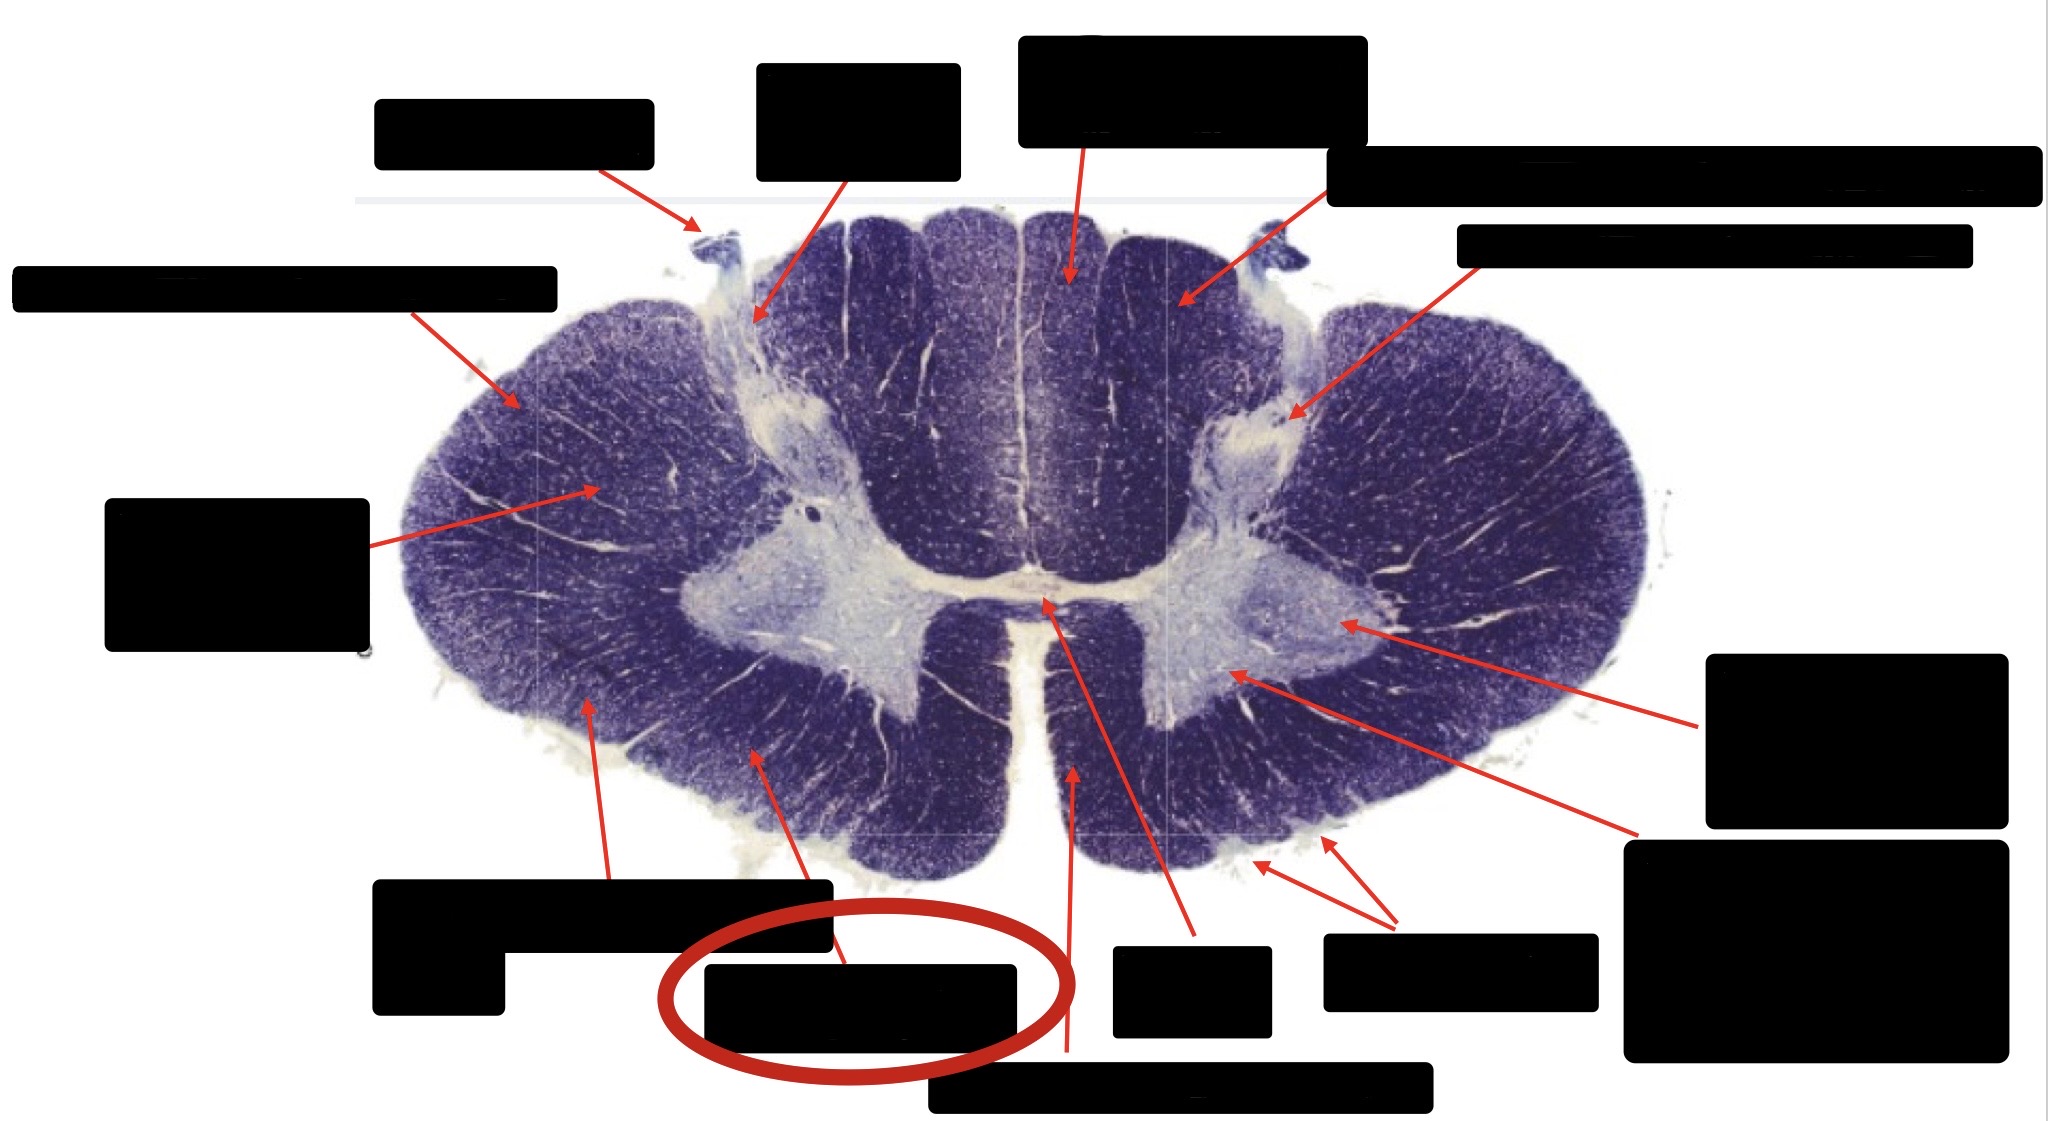

Central Canal

Anterior Corticospinal Tract

Posterior Column (Fasciculus Gracilis)

Posterior Column (Fasciculus Cuneatus)

Substantia Gelatinosa

Accessory Nerve Fibers

Anterior Horn Motor Fibers (Accessory Muscles)

Anterior Horn Motor Fibers (Proximal Muscles)

Ventral Root Fibers

Anterior Horn Motors Neurons (Proximal Muscles)

Posterior Columns (Joint Position, Vibration, Pressure)

Fasciculus Cuneatus

Fasciculus Gracilis

Dorsal Root

Dorsal Spinocerebellar Tract

Ventral Spinocerebellar Tract

Lateral Spinocerebellar Tract (Pain & Temperature)

Ventral Root

Anterior Horn (Motor Neurons)

Distal Limb Movements

Lateral Corticospinal (Pyramidal Tract)

Rubrospinal Tract

Axial & Proximal Limb Movements

Lateral Reticulospinal Tract

Vestibulospinal Tract

Ventral Reticulospinal Tract

Tectospinal Tract

Ventral Spinthalamic Tract (Pressure Touch - Minor Role)

Ventral (Uncrossed) Corticospinal Tract (Distal Limb Movements - Minor Role)